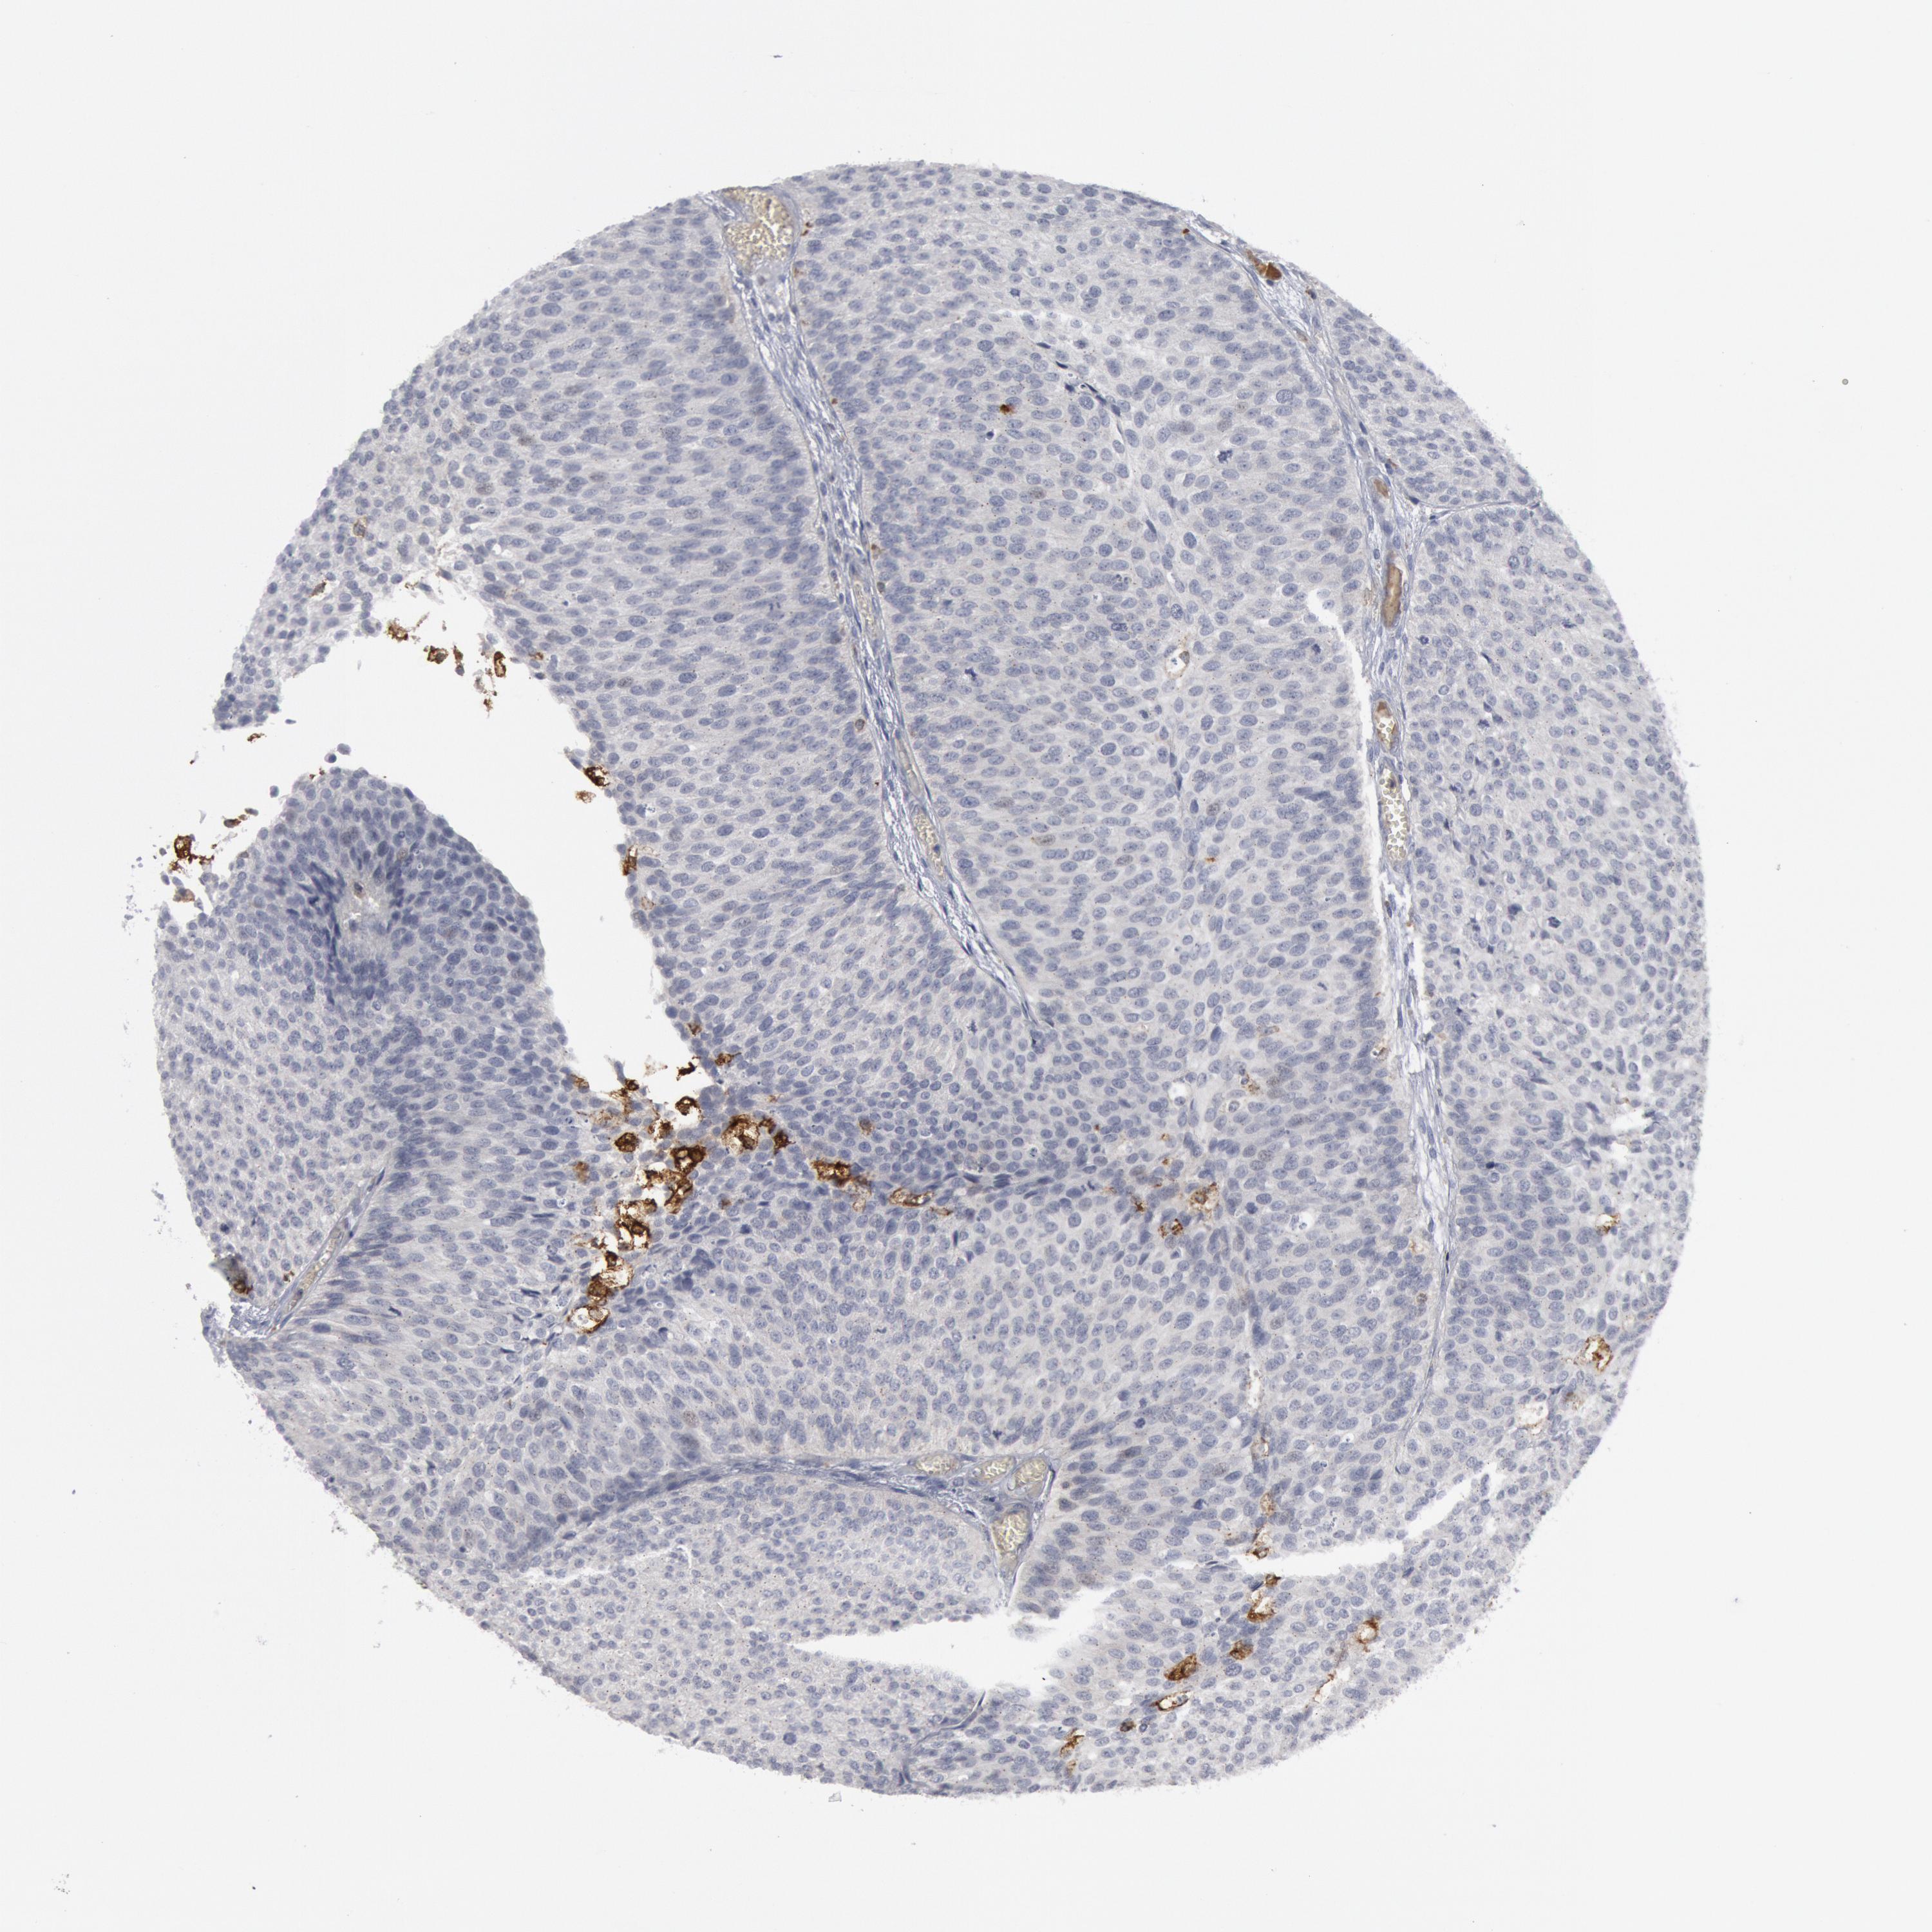

UROTHELIAL CANCER - Protein expressioni

A mouse-over function shows sample information and annotation data. Click on an image to view it in a full screen mode. Samples can be filtered based on level of antibody staining by selecting one or several of the following categories: high, medium, low and not detected. The assay and annotation is described here.

Note that samples used for immunohistochemistry by the Human Protein Atlas do not correspond to samples in the TCGA dataset.

Antibody stainingi

Antibody staining in the annotated cell types in the current human tissue is reported as not detected, low, medium, or high, based on conventional immunohistochemistry profiling in selected tissues. This score is based on the combination of the staining intensity and fraction of stained cells.

Each image is clickable and will lead to virtual microscopy that enables deeper exploration of all samples and also displays staining intensity scores, fraction scores and subcellular localization as well as patient and tissue information for each sample.

Antibody HPA001471

Antibody CAB009828

Staining

High

Medium

Low

Not detected

Intensity

Strong

Moderate

Weak

Negative

Quantity

>75%

75%-25%

<25%

None

Location

Nuclear

Cytoplasmic/membranous

Cytoplasmic/membranous,nuclear

Urothelial carcinoma, High grade